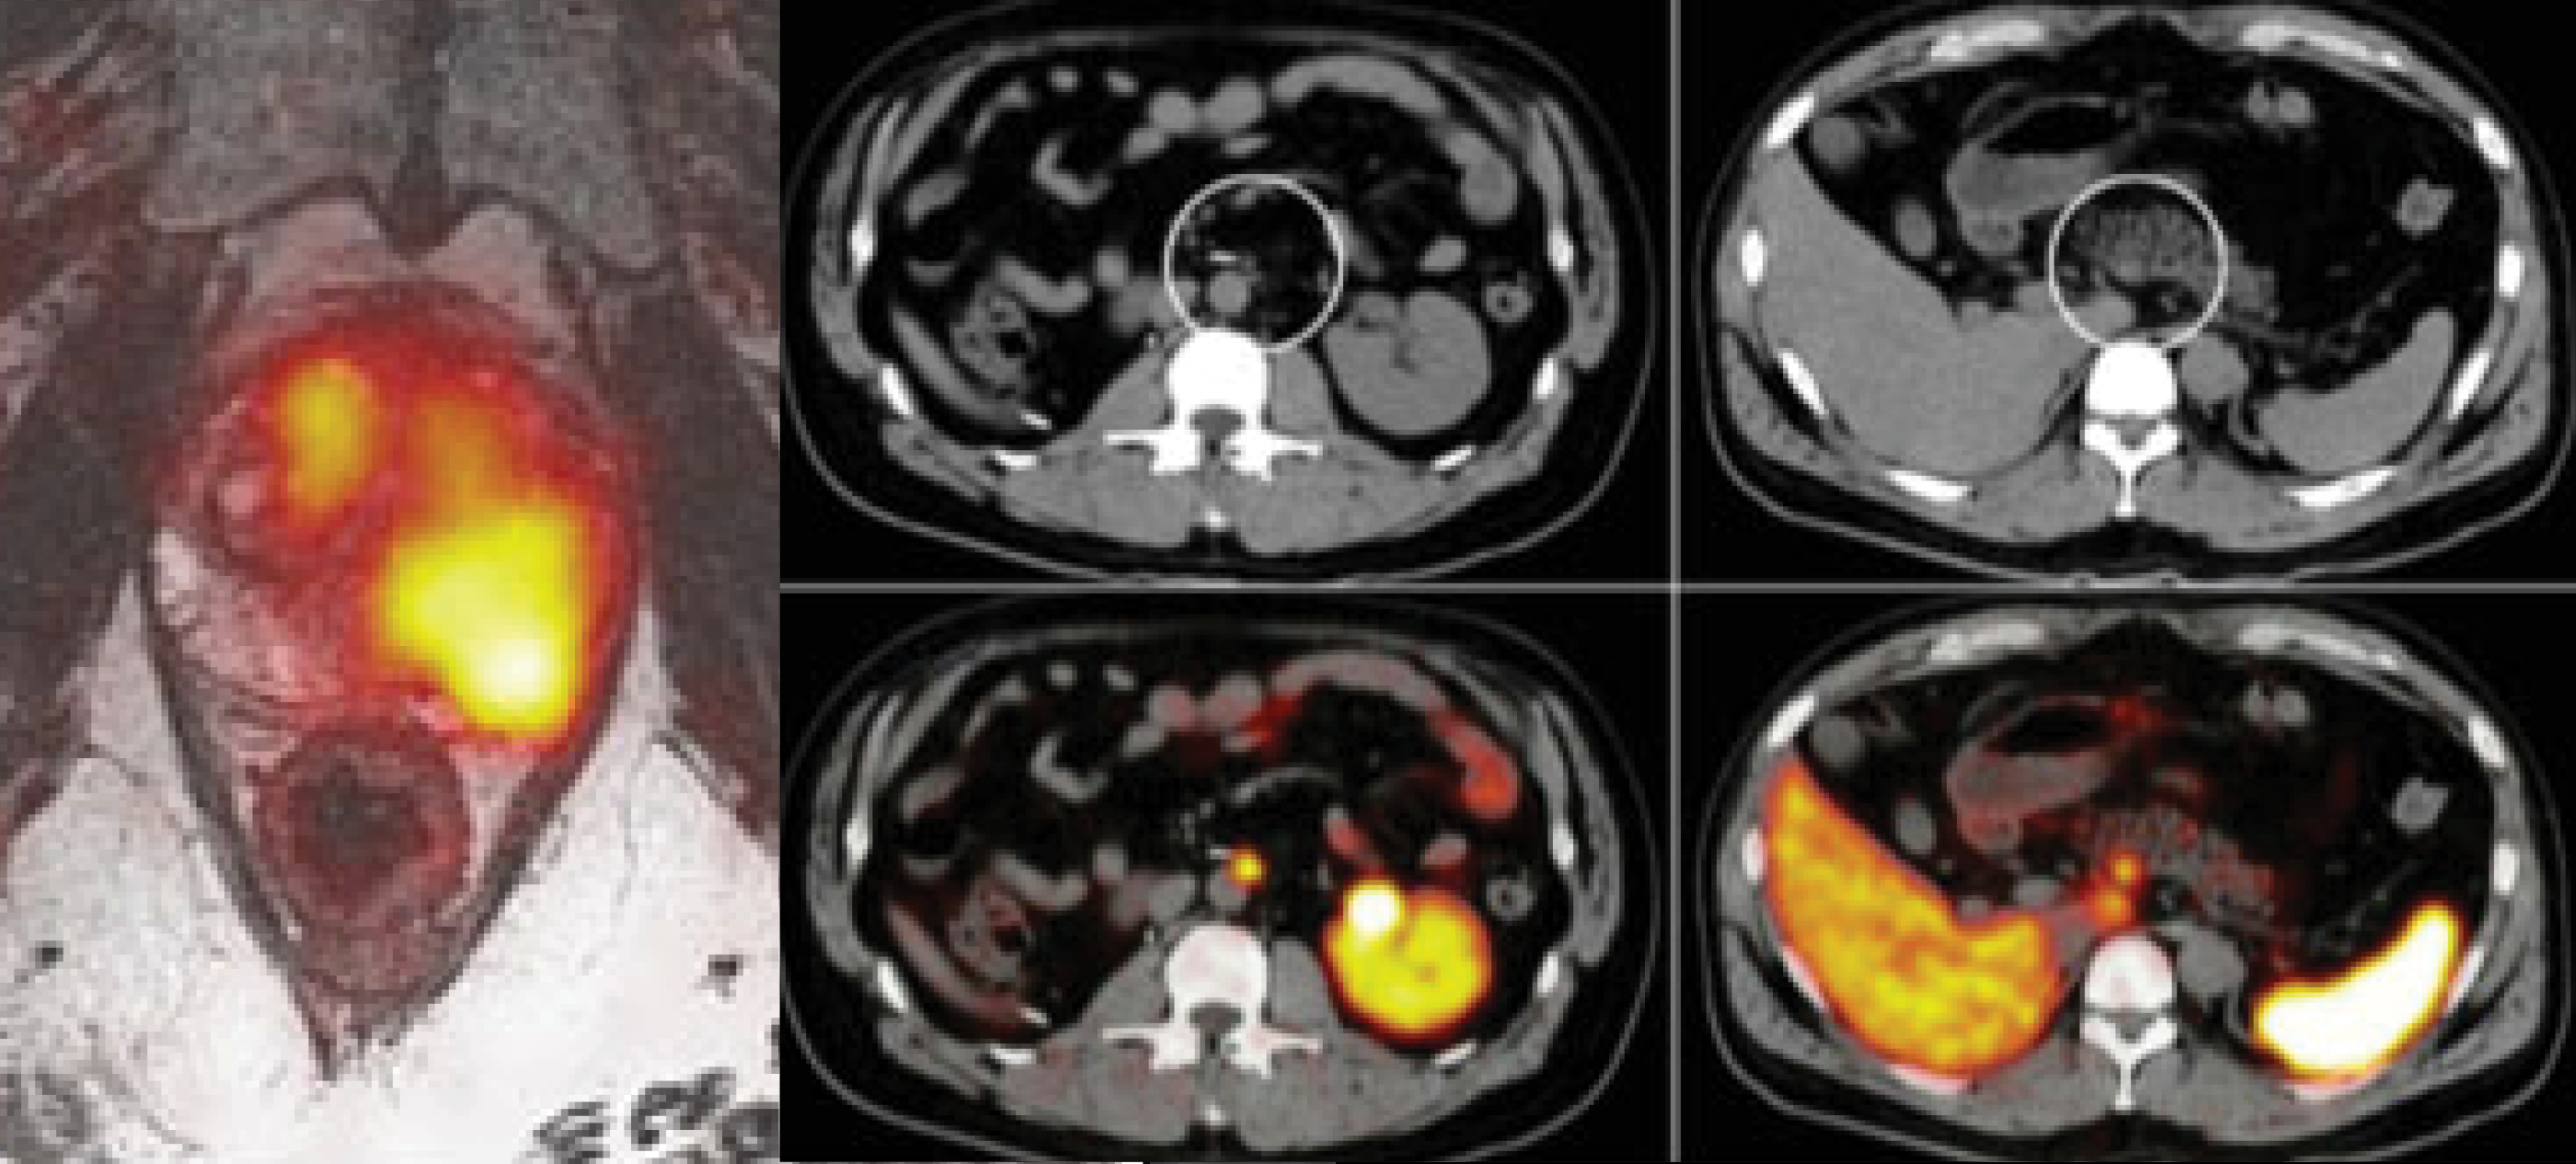

Series of PET and MRI fusion images showing radiotracer uptake in different body regions, illustrating metabolic activity and imaging contrast used in molecular imaging and radiochemistry research.

The Program for Molecular Imaging and Targeted Therapy Lab involves a number of clinical trials focused on the translation of novel targeting imaging and therapy agents. We have a strong translation clinical research focus on novel radiotracers and targeted radionuclide treatments. We also work on clinical applications of simultinaneous PET/MRI.

The simultaneous modality, PET/MRI, is a challenging environment due to the limitations of bringing PET and MRI together, but when appropriately leveraged, PET/MRI offers significant…